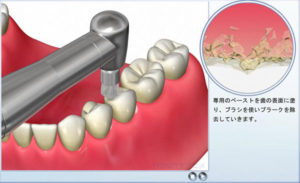

All-on-4 (6)のプロフェッショナルケア

3〜6ヶ月に一度は歯科医院で状態の確認と

清掃を行います。

ご自身でのケアでは限界がありますので、専用の道具を用いて、汚れを徹底的に落としていきます。

また、使用により

かみ合わせに変化が生じることがありますので、かみ合わせを確認し、調整することがあります。

上部構造物に汚れがつきます。

通常の歯ブラシで磨いてください。ただし、研磨剤の入った歯磨き粉を使用すると、表面に細かい傷がつき、着色や細菌がつきやすくなりますので、注意が必要です。

歯肉と上部構造物の間に食べ物が挟まったり、汚れが溜まりますので、この部分の清掃が重要です。

歯間ブラシやスーパーフロス、ウォーターピックを用いて、汚れを落としましょう。